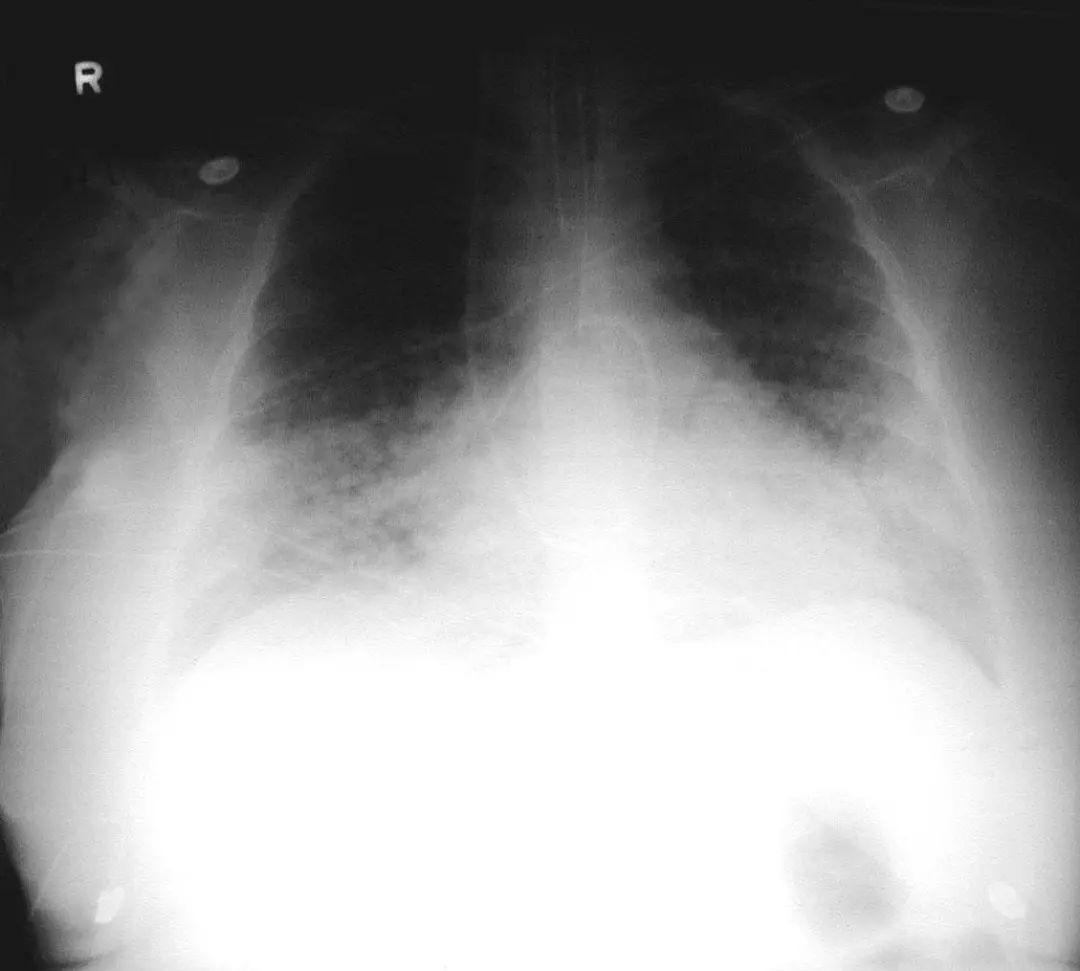

图1.2 细菌性肺炎。双肺下叶肺炎患者影像。